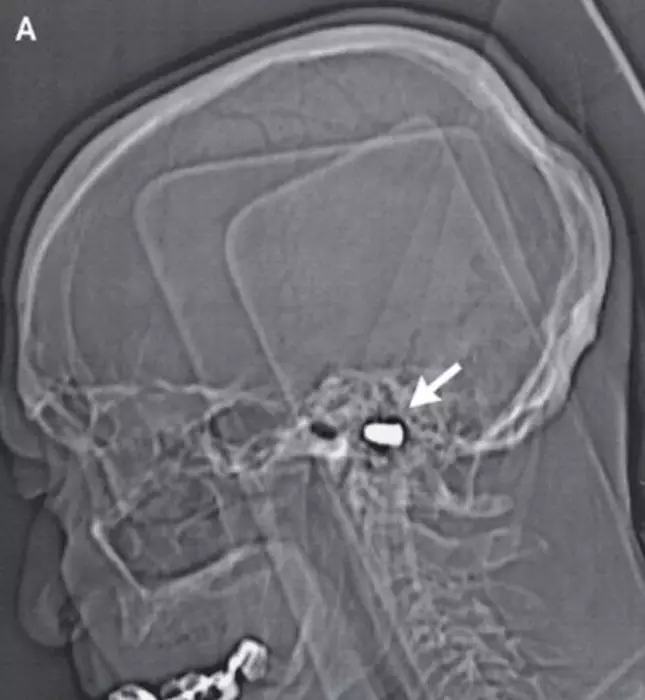

Россиянин прожил 82 года с пулей в голове Рентгеновский снимок раненного в голову мужчины. Фото с сайта nejm.org

Россиянин прожил с пулей в головном мозгу 82 года, сообщает New England Journal of Medicine. Однако данные пациента не уточняются. В пострадавшего стреляли, когда ему было три года. Пуля прошла под носом и остановилась в основании черепа, не задев спинной мозг. Медики опасались оперировать ребенка, считая, что хирургическое вмешательство может вызвать непоправимые осложнения. "Организм детей обладает потрясающей способностью к самоизлечению", - сказал доктор Ричард О'Брайан (Richard O'Brien), комментируя беспрецедентный случай. В возрасте 85 лет мужчине сделали операцию на сердце. Хирурги обнаружили инородный предмет в черепе мужчины во время изучения рентгеновских снимков. Но извлекать пулю они все же не решились. Примечательно, что все это время пуля не причиняла дискомфорта раненому. Отмечается также, что травма не отразилась на его умственных способностях, мужчина построил свою карьеру в сфере строительства баллистических ракет.